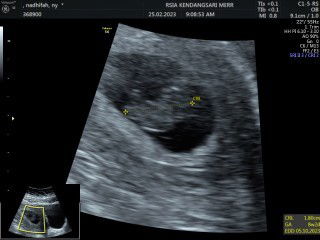

Biasanya aku kalo USG ke dokter obgyn, karena aku kangen pingin liat dede tp jadwal usg baru 2 minggu lagi, jadinya aku perdana USG di puskesmas di uk.10w3d Ngga disangka2 meskipun yg meriksa dokter umum, aku dan suami sangat puas dengan penjelasan dokter saat usg. Dokternya sangat baik dan ramah, dia menjelaskan detail ini apa itu apa, kita nanya dan dijawab serta ditunjukkan. Tadi saat usg suami nanya, dok itu janinnya udh gerak apa blm yaa ? Trs diliatin, ini liat yaa pak alat usg nya kan diem nih, tuh2 gerak kan.. eh iya bayinya lompat dong salto kek asik bgt berenang didalem, aku sama suami ngakak disitu wkwk Lucuu bgt maa sya Allah 🥰 Pdhl kalo ke obgyn mah cepet yaa usg nya, tadi tuh ada kali 30 menit usg nya doang.. puasss pokoknya, suami jg sueneng liat dede gerak2 #baby10weeks #usg #sharing